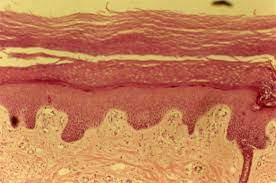

Se distinguen epidermis, dermis e hipodermis. La epidermis es un epitelio plano, estratificado, queratinizado, formado por cinco estratos:

1.Basal o germinativo, constituido por una hilera de células cilíndricas basófilas: los queratinocitos. Aquí se inicia la proliferación de estos últimos, unidos entre sí por desmosomas, y a la membrana basal por hemidesmosomas. Cada 5 a 10 queratinocitos se intercalan células dendríticas (melanocitos) y no dendríticas (células de Merkel) y en la región suprabasal, las células de Langerhans. Hay un melanocito por cada 30 a 40 queratinocitos y conforman la unidad melánica-epidérmica. Los melanocitos contienen melanosomas y en su interior melanina, que transfi eren a las células vecinas. La célula de Langerhans es una célula presentadora de antígenos que proviene de la médula ósea y pertenece al sistema de macrófagos-mononucleares; contiene gránulos o cuerpos raquetoides (de Langerhans o de Birbeck). La célula de Merkel forma parte del sistema celular endocrino difuso que funciona como mecanorreceptor y tiene relación con terminaciones nerviosas sensitivas.

2. Espinoso o de Malpighi, compuesto por varias capas de células poliédricas unidas entre sí por puentes intercelulares o desmosomas; consta de células con granulaciones de queratohialina (precursor de la queratina) hematoxilínicas.

3 . Lúcido, que sólo se presenta en piel muy gruesa, como la de las palmas y plantas; está formado por eleidina.

4. Córneo, muy grueso en las palmas y plantas, integrado por células muertas aplanadas y sin núcleo, que contienen una proteína fibrilar, la queratina.

La unión de la epidermis y la dermis no es plana, sino que presenta ondulaciones dadas por las papilas dérmicas y las crestas interpapilares epidérmicas. Entre la capa basal y la dermis se encuentra uno de los sitios más fascinantes de la piel, la membrana basal epidérmica. Hoy se sabe que muchas de las enfermedades ampollares adquiridas y congénitas son causadas por anticuerpos o mutaciones que se producen en algunos componentes de este pequeño mundo de antígenos. La membrana basal epidérmica se divide en las siguientes zonas: a) membrana celular de la célula basal, que es positiva a PAS; b) lámina lúcida, constituida por el antígeno del penfigoide (AgPA2, colágeno XVII), el antígeno de la enfermedad por IgA lineal (AgLAD), laminina y epiligrina; c) lámina densa y sublámina densa; entre estas dos están las fibrillas de anclaje y el antígeno de la epidermólisis ampollar (AgEA). El AgPA1 es parte del hemidesmosoma, y el AgPA2, de la lámina lúcida; el colágeno tipo IV que se localiza en la lámina densa es el antígeno en el lupus eritematoso discoide, y el colágeno tipo VII, que forma las fibrillas de anclaje, es el antígeno de la epidermólisis ampollar adquirida. Asimismo, la mutación de los genes que codifican para colágeno tipo VII genera las epidermólisis ampollares distróficas congénitas.

La dermis se clasifica en superficial o papilar media o reticular y profunda. Está compuesta de tejido conjuntivo, vasos, nervios y anexos cutáneos. Hay tres clases de fibras proteínicas: de colágeno, reticulares y elásticas; una sustancia fundamental formada por mucopolisacáridos y varios tipos de células: fibroblastos (que producen colágeno, sustancia fundamental y colagenasa), histiocitos, mastocitos, polimorfonucleares, eosinófilos y plasmocitos. Del colágeno se reconocieron inicialmente cinco componentes moleculares (I a V), pero a la fecha la descripción se ha extendido hasta el colágeno XVII; el componente I se distribuye en la piel, los huesos, los tendones y ligamentos; el II en el cartílago; el III en la piel fetal, y el IV en la membrana basal.